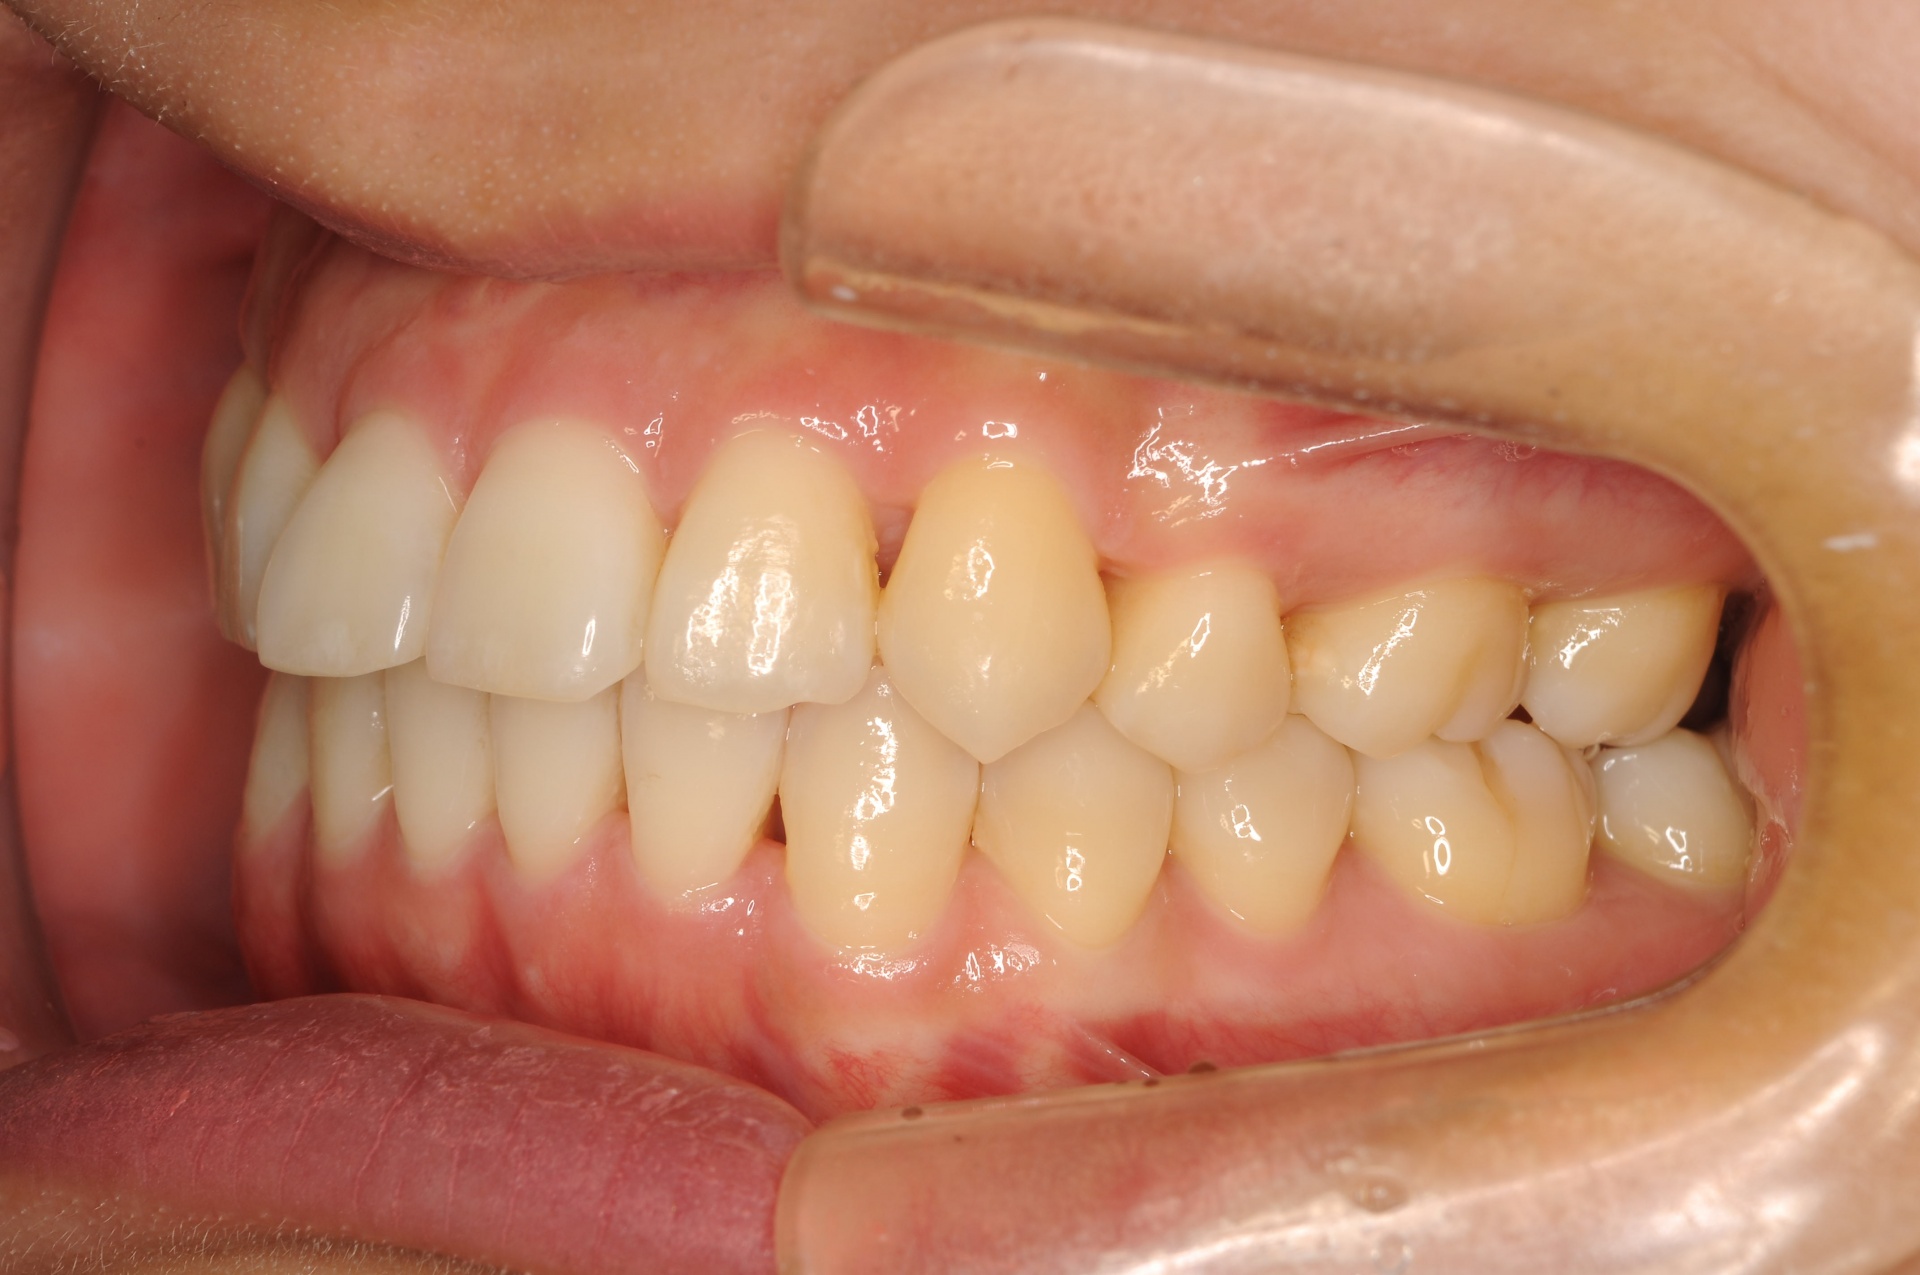

治療前

上顎両側犬歯が唇側で上方に萌出していることと、下顎前歯部の叢生を主訴に来院された20代の女性です。

治療後

上下の正中は一致し、上顎両側犬歯は歯列内に誘導されました。奥歯の咬合関係は緊密で、再配列されたことにより機能・審美ともに改善されました。